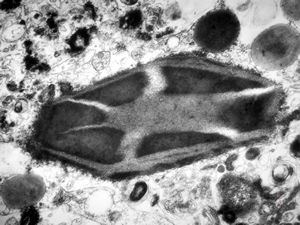

M,41y. | ribosome-lamella complex in tricholeukocyte -hairy cell leukemia, spleen

M,41y. | ribosome-lamella complex in tricholeukocyte -hairy cell leukemia, spleen

M,41y. | ribosome-lamella complex in tricholeukocyte -hairy cell leukemia, spleen